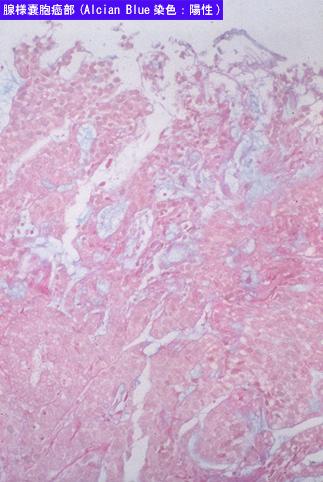

clasificación del pacienteTumor Epitelial Maligno/Carcinoma a Células Escamosas

método de exámenMicro

clasificación ectoscópica de tumoresTipo 2(Tipo ulcerado de bordes claros)/

grado de penetracións(a)